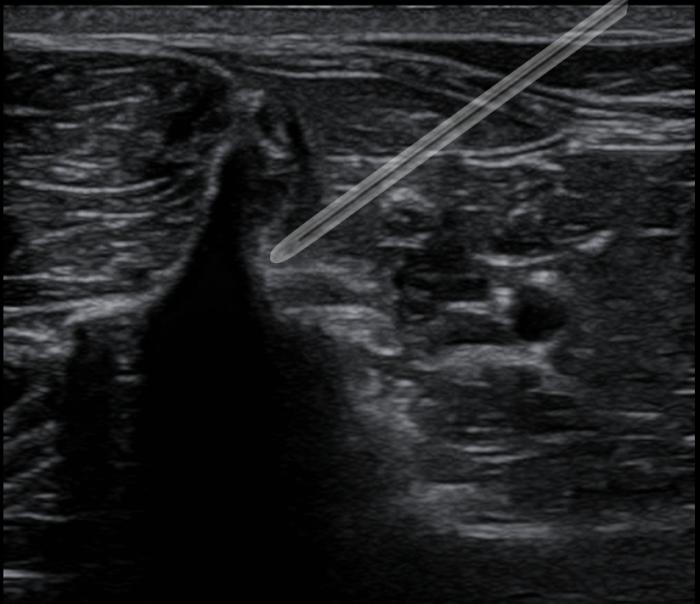

Se prepara el bloqueo a una dosis de 0.3 ml/kg para el bloqueo del GIN y una dosis de 0.5 ml/kg para el bloqueo del cuadrado lumbar caudal. Calculado los bloqueos las dosis en volumen quedarían así:

- Bloqueo GIN: 0.75 ml sitio.

- Bloqueo TONIC: 1.25 ml sitio.

- Volumen total para bloquear = 2 ml.

Sabiendo esto se calcula el bloqueo a una dosis de 2 mg/kg gato de bupivacaína. En México la bupivacaína disponible viene en presentación del 0.5 % por lo que si la llevamos a una dosis de 0.25 % obteniendo así los 2 ml de volumen de bloqueo totales.

Para diluir la bupivacaína del 0.5 % para dejarla al 0.25 % se debe agregar una parte de bupivacaína y una parte de agua estéril o solución salina. Como ejemplo, si al paciente le tocaba 1 ml de bupivacaína al 0.5 % según sus dosis se le agrega 1 ml de salina y así dejamos 2 ml de bupivacaína al 0.25 %.

A esto se sumó dexmedetomidina a una dosis de 1 mcg/kg sitio y triamcinolona a dosis de 0.15 mg/kg sitio. El total en ml de cada medicamento solo se le administra al total de medicamento para el bloqueo. Agregándole así 0.5 ml de dexmedetomidina (100 mcg/ml) y 0.125 ml de triamcinolona (6 mg/ml).

La dosis de volumen total del bloqueo ya con los coadyuvantes fue de 2.61 ml y se realizó al final una aplicación a cada punto un total de 1.7 ml para el TONIC y 0.92 ml al GIN (Figura2-4, Vídeo 2) .